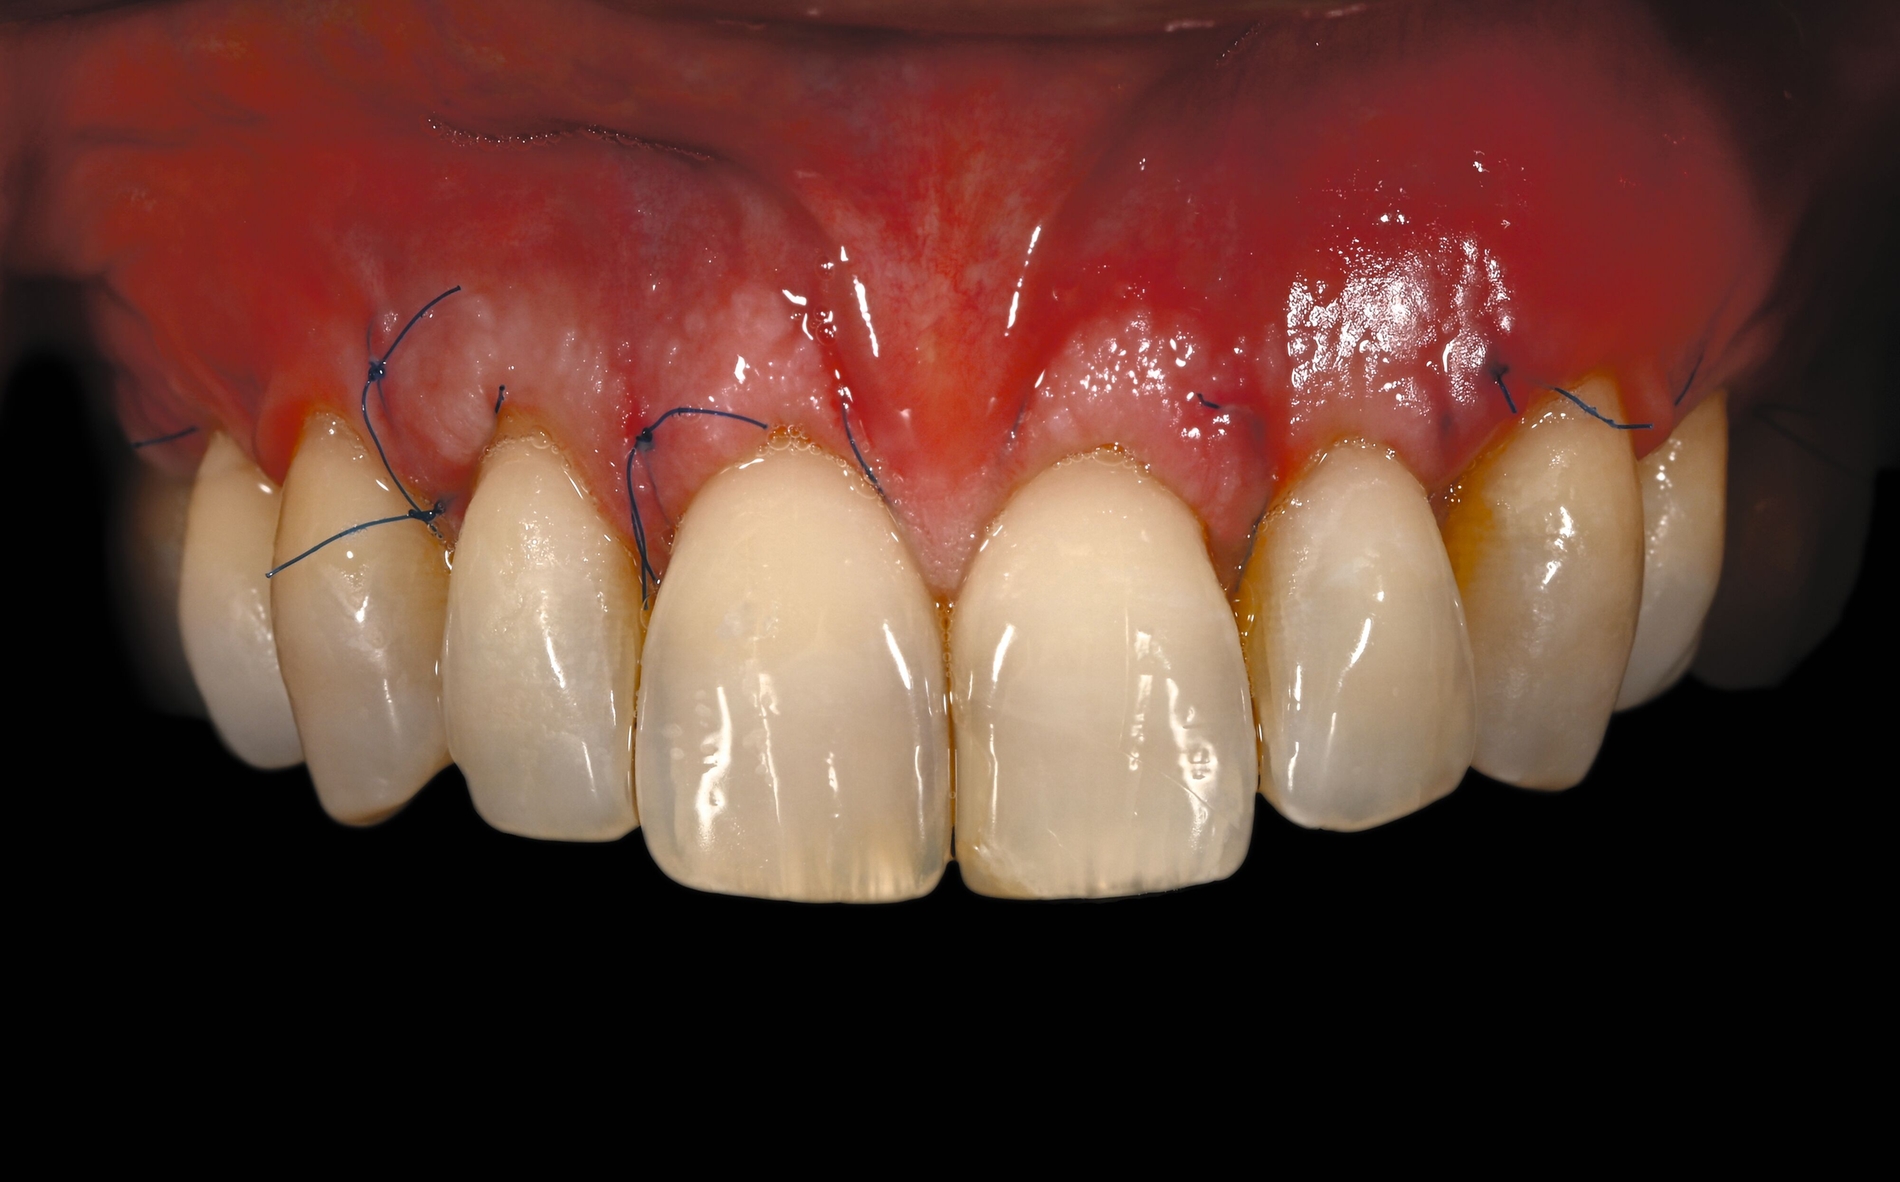

Trotz des Verbleibs des Epithels kann es zu sekundärer Wundheilung mit entsprechender Morbidität postoperativ kommen, besonders bei Techniken, die mehrere Inzisionen beinhalten, wie den sogenannten Trap-Door-Techniken, so dass sich die „Single-Incision-Technik“ durchgesetzt hat [Fickl et al., 2014]. Gegen eine übermäßige Blutung und postoperative Morbidität empfiehlt sich klinisch die routinemäßige Anwendung einer Verbandplatte, entweder in der Tiefziehtechnik oder präoperativ mittels eines Thermoplasts, so dass sich früh ein stabiles Blutkoagel bildet und die Wundheilung an der Entnahmestelle ungestört ablaufen kann. Dadurch wird die Morbidität klinisch deutlich reduziert. Das sBGT zeigt ästhetisch sehr gute Ergebnisse mit Blick auf Oberflächenstruktur sowie Farbe und kann unter anderem im Rahmen der Envelope- oder Tunneltechnik oder auch über einer Extraktionsalveole bewusst exponiert belassen werden, um zusätzlich befestigte Gingiva zu gewinnen.

Die Wundheilung nach dieser Technik erfolgt anders als beim sBGT immer sekundär, somit wurden bei Vergleichsstudien eine signifikant erhöhte Morbidität, Schwellungen und ein erhöhtes Nachblutungsrisiko beschrieben [Del Pizzo et al., 2002; Griffin et al., 2006], was jedoch bei entsprechender Versorgung des Gaumens umgegangen werden kann [Zucchelli et al., 2010]. Die Versorgung der Spenderregion kann mit Kollagenvlies, Cyanoacrylatkleber, Verbandplatte oder einer Kombination erfolgen. Dies kann die Morbidität deutlich reduzieren [Tavelli et al., 2019b]. Ein Vorteil von dBGT ist die Stabilität der Gewebedicke im Laufe der Zeit, was im Gegensatz zur beschriebenen Schrumpfung von sBGT steht, die häufig beobachtet wird [Zucchelli et al., 2018].

Eine Übersichtsarbeit, die sBGT und dBGT im Rahmen der Rezessionsdeckung verglich, empfahl primär die Anwendung des dBGT. So lag die mittlere Wurzelabdeckung nach zwölf Monaten mit dem sBGT bei 89,3 Prozent im Vergleich zu 94 Prozent beim dBGT. Die Daten der dBGT-Gruppe stützten sich jedoch nur auf die Ergebnisse einer einzigen Arbeitsgruppe und die Gruppen mit der höchsten durchschnittlichen Wurzeldeckung wurden für das sBGT berichtet, so dass hier ein gewisser Centereffekt vermutet werden kann. Weiterhin besteht bei dBGT ein gewisses Risiko für ästhetische Komplikationen wie eine keloidartige Narbenbildung, eine unnatürliche Randsituation oder eine deutlich hellere und glattere Oberfläche, wenn das Transplantat nicht korrekt gehandhabt wird, der Decklappen sehr dünn ist oder das Transplantat offen einheilt [Gluckman et al., 2019; Zucchelli et al., 2014b].

Neuere Daten haben weiterhin gezeigt, dass die Durchblutung des Decklappens durch ein dBGT signifikant länger reduziert ist als bei einem sBGT, was in der Folge zu häufiger auftretenden späten Komplikationen wie Zystenbildungen führt [Ragghianti-Zangrando et al., 2021]. Die vollständige Entfernung des Epithels – egal ob intra- oder extraoral – wird nicht immer erreicht [Couso-Queiruga et al., 2023], was letztlich zu Problemen bei der Einheilung mit unvollständiger Verbindung zum Decklappen oder mit der Wundunterlage wie der Wurzeloberfläche führen kann. So wurde von einer deutlich erhöhten Dehiszenzrate in etwa jedem zweiten Fall bei dicken dBGT (> 1,5 mm) mit entsprechend reduziertem ästhetischem Ergebnis berichtet [Zucchelli et al., 2014a].